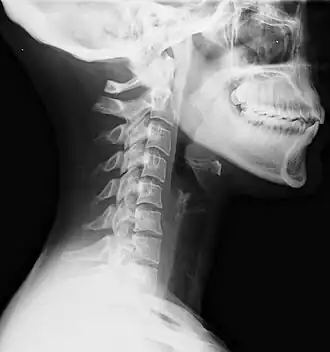

Radiographie cervicale de coup de lapin montrant une perte de la lordose normale.

Le coup du lapin est un traumatisme du rachis cervical, qui peut être dû au mouvement de la tête ou à un coup porté.

Traumatisme indirect

Il s'agit dans ce cas d'un traumatisme indirect du rachis cervical en flexion-extension, en général lors d'un accident dans un véhicule brutalement arrêté. Il produit plutôt des entorses du rachis cervical, habituellement bénignes, mais pas toujours. Il peut également produire des fractures, particulièrement des fractures du corps en compression. Pour l’éviter, les véhicules sont équipés d'appui-têtes.